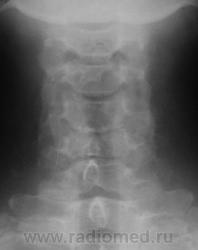

Уважаемые коллеги! Данные снимки произведены вне какой-либо связи с травмой или жалобами на боли. Просто такая картинка встречается довольно часто. Как Вы для себя интерпретируете такие деформации задних углов тел позвонков? Могут ли они вызывать неврологические жалобы? Является ли это следствием остеохондроза? На мой взгляд, на краевые костные разрастания в обычном их понимании это мало похоже.

На рентгенограммах шейного отдела позвоночника в 2-х проекциях определяется сглаженность физиологического лордоза,  снижение высоты межпозвонковых дисков на уровне С4-5 2 ст., С5-6 1 ст., уплотнение замыкательных пластинок, скошенность передневерхних углов С3-7, деформация тела С4, передние осеофиты тел С4-С6, задние С5-6, остеофиты унковертебральных сочленений. Явления субхондрального склероза межпозвоночных суставов.

Норма.Вариант строения лимба тел позвонков.Выпрямленность лордоза может быть следствием укладки. Диаметр корешка и диаметр спинно-мозгового отверстия в шейном отделе позвоночника соотносяться как 1:16 , если не ошибаюсь, т.е. 16-кратный запас прочности, для компенсации заложен природой в случае подобных конфликтов(компрессия корешка).Корешковые синдромы на шейном уровне редкость.Тем более клиники нет. О чём вести речь.Скверно,коллеги, когда мы свои умозрительные представления искренне подаём как истину.